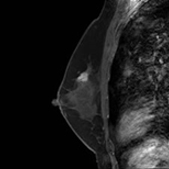

画像中间浅淡白色部分为癌 (治疗前)

治疗6个月后,白色部分变小

治疗一年后白色部分有明显缩小的变化